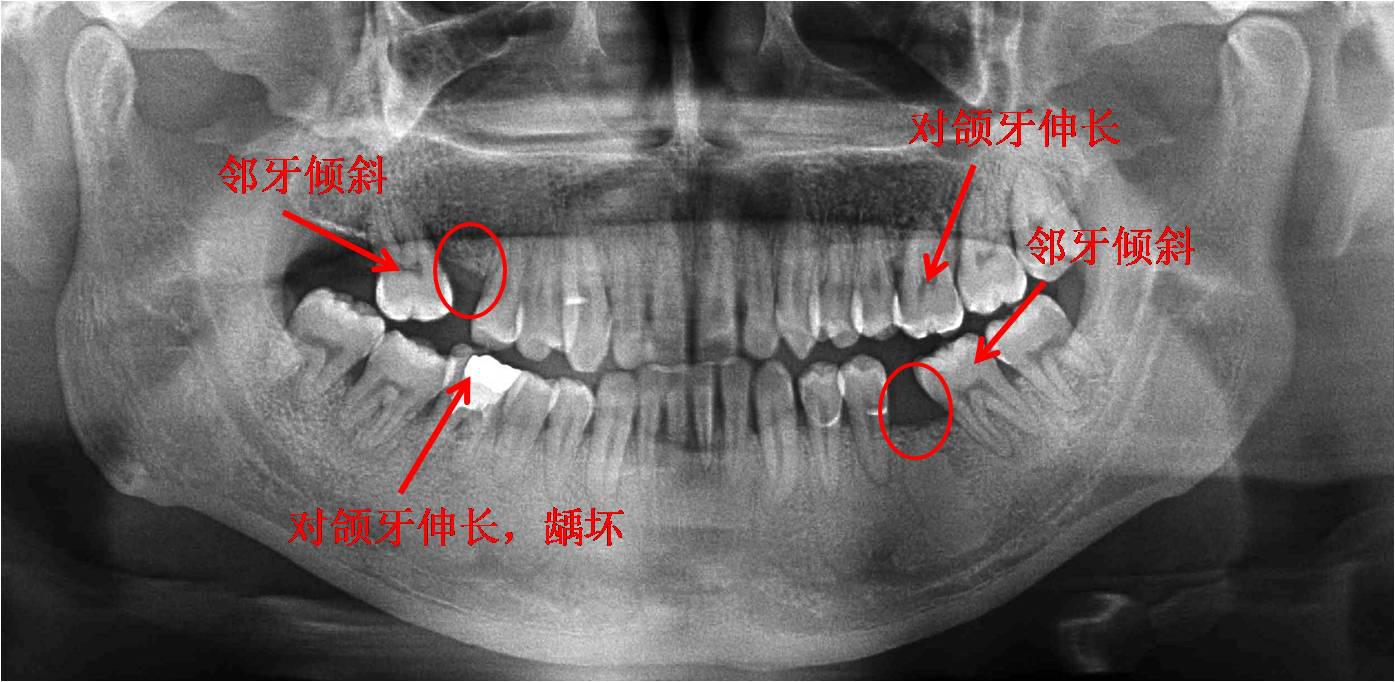

一、“六龄齿”的重要性:“六龄齿”位于整个牙弓的中部,是最早萌出的恒牙,成为牙弓的主要支柱,对于保持上下颌牙齿的正常排列,维持正确的咬合关系以及保证颌面部的正常发育都具有重要意义。“六龄齿”的过早龋坏甚至拔除,不仅大大降低儿童的咀嚼功能,造成儿童营养不良,还会影响颌骨的发育,引起邻牙倾斜以及对颌牙的伸长造成咬合关系紊乱,对儿童的身心健康造成很不利的影响。